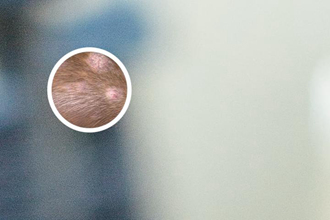

白点病图片早期的更明确特征是皮肤上出现白色斑点。这些斑点的大小和形状各不相同,有些可能呈圆形,而另一些可能呈不规则形状。这些斑点通常较小,直径一般在数毫米之内。当白点病图片早期的斑点出现在肤色较暗的部位时,会更加显眼。

2. 颜色变化:白点病图片早期的白斑一般呈现出明确的白色,与周围正常皮肤形成鲜明对比。这种颜色变化常常让人感觉不适,给患者心理上带来一些压力。

3. 边界清晰:白点病图片早期的白斑与周围正常皮肤的边界一般比较清晰,没有模糊不清的过渡区域。这一点是与其他一些皮肤疾病不同的地方。

4. 触感正常:白点病图片早期的白斑通常没有明确的瘙痒、疼痛或刺激感。与其他皮肤疾病相比,患者在触摸白斑时一般不会有太明确的感觉异常。